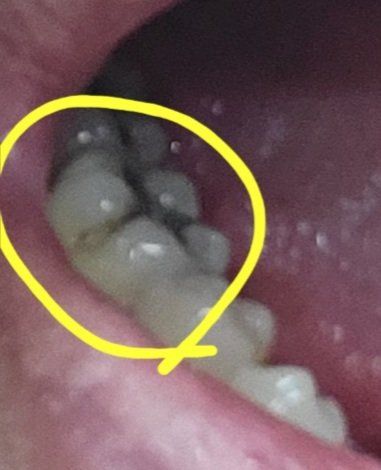

10년 넘은 충치치료한 땜이 떨어졌는데 레진? 크라운? 어떤걸 해야하나요?

어릴적 충치치료 했던 어금니 땜(?)이 떨어졌습니다

거울로 보니 옆쪽부분인데, 레진치료 가능한지 크라운 치료 해야하는지 궁금합니다

아말감이 부분적으로 떨어진것같습니다.

오래전에 아말감으로 치료한 것 중 일부가 깨져서 떨어진 것으로 보입니다.

사진만으로 치아의 정확한 상태를 판단하기는 어려우나, 해당 부위를 치료하기 위해서는 씹는 면의 아말감도 모두 제거해야 할 것으로 보입니다.

치아 옆면이기는 하지만 기존 아말감과 연결되어 있는 부위로, 아말감과 레진은 접착하지 않기 때문에 단순히 레진으로 치료하는 경우에는 누출이 발생하여 레진 접착 실패나 2차 충치가 유발될 수 있기 때문입니다.